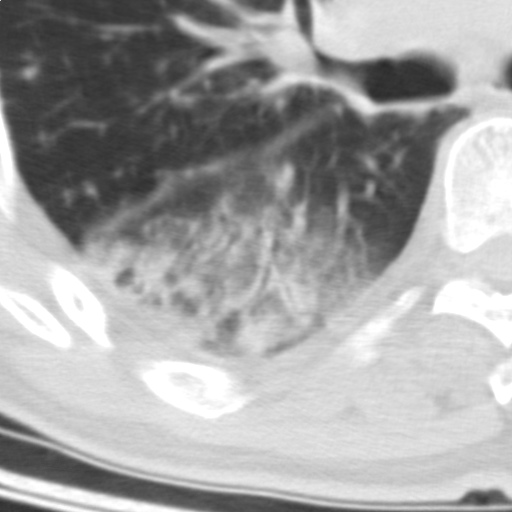

以下是引用随光逐影在2009-5-1 13:53:00的发言:[br]考虑为:1)两肺血行播散型肺结核;2)右肺下叶炎症感染。3)右侧胸膜增厚。